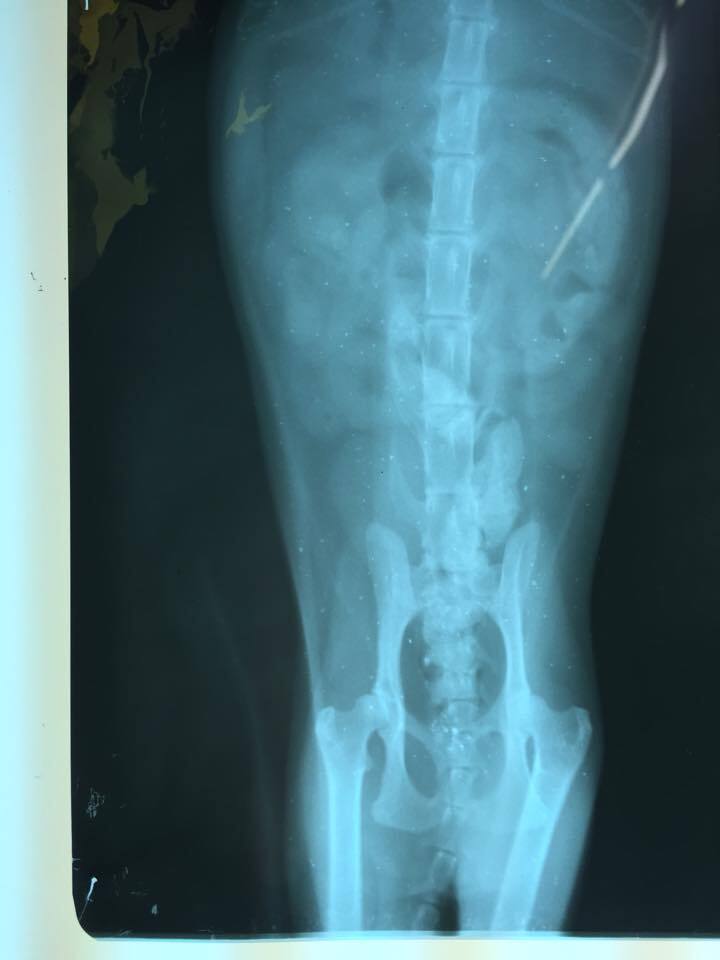

主題: 脫水虛弱走路不穩虎斑貓 申請者姓名: 許桂菱 花色: 申請日期: 2015-03-17 23:56:34 申請者部落格: 申請者臉書網址: 所在縣市/合作醫院: 彰化縣/成愛動物醫院 治療費用: 5230元 需求人數: 6人 已結案 (2015-04-14 17:29:36) 報名人員: fotojo(已付款)、Shu-Chun Yu(已付款)、黃小語(已付款)、陳昱先(已付款)、Tiffany Cheung x2(已付款)、 候補人員: 動物病情說明: 此母貓在餵養區不見蹤影10來天,本以為可能發生意外往生,3/5下班如常至餵養區,她卻出現但脫水消瘦及走路不穩歪斜,一度以為是否為後腳受傷,趕緊先向住戶要了紙箱,送醫檢查後醫生認為非腳傷,進行生化及二合一血檢,有貧血其他指數無特別異常,快篩有愛滋,貓無發燒但脫水虛弱無法自行進食,先施予點滴改善脫水及住院觀察!

3/10~3/12 照X光片確認骨頭沒有受傷,身體也無外傷,貓咪恢復自行進食,但是行走仍無力歪斜,醫生認為是神經問題,先補充B群營養

3/13出院帶至台中羅大宇醫院看診是否能做針灸治療,醫生認為可能是愛滋病毒造成的神經受損,目前以補充B群及改善貧血為優先!